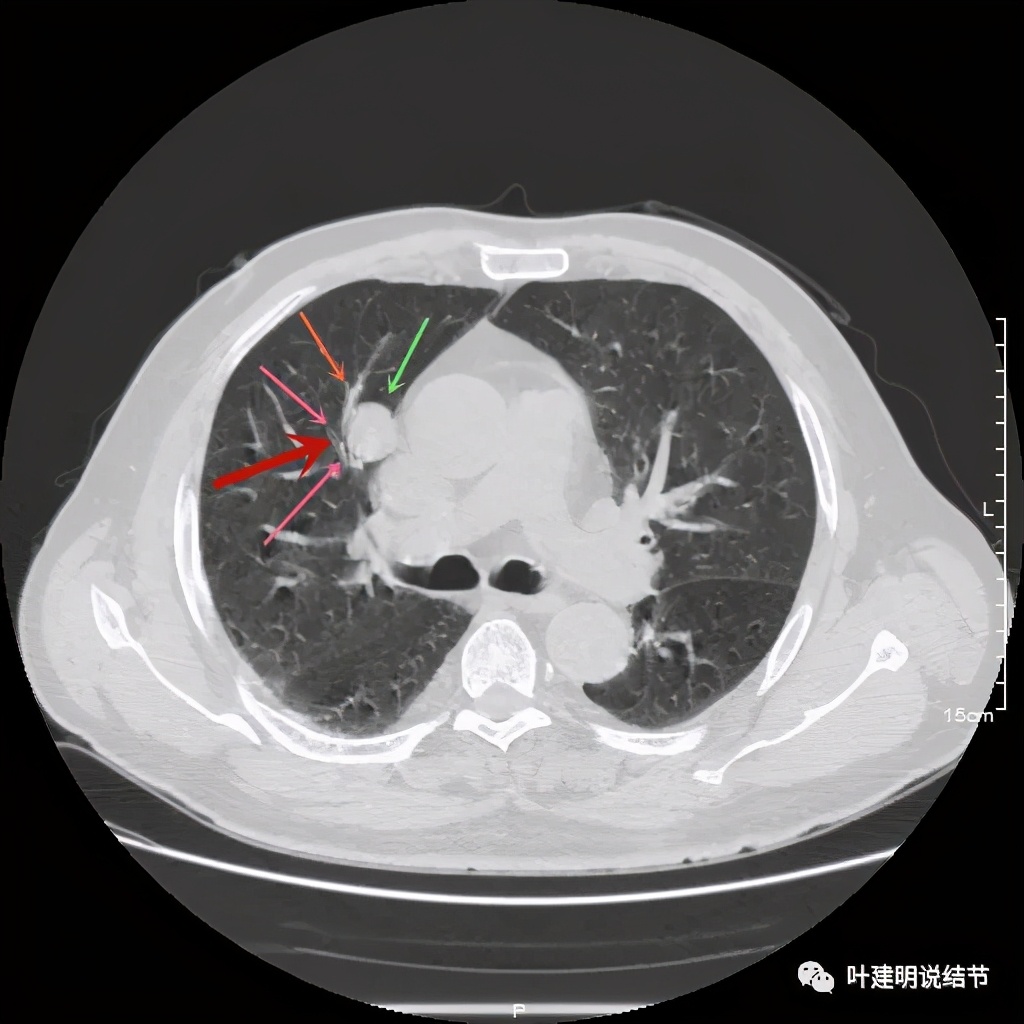

上图示病灶边缘过于光滑(绿色);血管贴边(桔色);

上图示病灶边缘过于光滑(绿色);血管贴边走行(桔色)

以上几图也示病灶边缘过光(绿色);血管贴边,感觉没受侵犯(桔色)

事前来看,达2.4厘米的不均质实性肿块,增强有轻度不均匀强化,血管贴边走行,支气管疑有截断,恶性不能除外,而且可能性较大。但现在经过手术已已经证实是错构瘤的情况下,我们回头来看,其实有许多不符合恶性的地方:

1、病灶的每个层面,边缘都过于光滑了。肺癌一般到这个大小总要有棘突、分叶、毛刺、牵拉周围胸膜等边缘异常的征象;

2、肿瘤大于2厘米以上,又紧贴血管,多有血管走行异常、受侵或血管进入等征象;